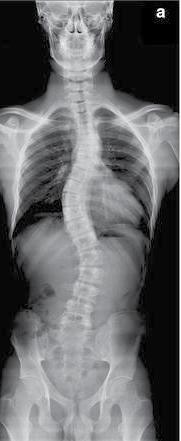

KIST ๋ฌธํ์ค ์ฐ๊ตฌํ, ๊ตญ์ ํ์ ์ง ๋ฐํ / ํ๊ฐ ์ฆ์ ์น๋ฃ๋ฒ ๊ฐ๋ฐ ๊ธฐ๋

์ฐ๋ฆฌ ๋ ์์์ GPS(์์น์ ๋ณด์์คํ )์ฒ

๋ผ ์์ ์ ์์น๋ฅผ ์ธ์งํ๋ ๊ธฐ๋ฅ์ ์ํ

ํ๋ '๊ฒฉ์ ์ธํฌ'(grid cell)๊ฐ ์ค์ ์ฅ์

์ด๋ ์์ด ์ ๋๋ ํ๊ฐ์๋ ๋ฐ์ํ๋ค๋

์ฐ๊ตฌ๊ฒฐ๊ณผ๊ฐ ๋์๋ค.

ํ๊ตญ๊ณผํ๊ธฐ์ ์ฐ๊ตฌ์(KIST) ๋ฐ์ด์ค๋์ค

์ฐ๊ตฌ์ผํฐ ๋ฌธํ์ค ๋ฐ์ฌ ์ฐ๊ตฌํ์ ์ค์์ค

๋ก์์ฐ๋ฐฉ๊ณต๊ณผ๋ํ ์ฌ๋ผํ ๋ธ๋์ผ ๊ต์

์ฐ๊ตฌํ๊ณผ ํจ๊ป ๋ค์ค๊ฐ๊ฐ ๊ฐ์ํ์ค(VR)์

์ด์ฉํด ์๊ธฐ ์์น ํ๊ฐ์ ์ ๋ํ๊ณ , ์ด๋ก

์ธํ ๋ ์ ๊ฒฉ์ ์ธํฌ ํ์ฑ์ ๋ณํ ๊ด์ธก์

์ฑ๊ณตํ๋ค๊ณ 14์ผ ๋ฐํ๋ค.

๋ ์ ๊ฒฉ์์ธํฌ์ ์ฅ์์ธํฌ(place cell)

๋ ์ฐ๋ฆฌ๊ฐ ํน์ ์ฅ์๋ก ์ด๋ํ๋ ๋์ ๋ฐ

์ํด ์ฐ๋ฆฌ์ ์์น๋ฅผ ์ขํ ํํ๋ก ์ธ์ํ

๊ณ ๊ณต๊ฐ ๋ด ์ฌ๊ฑด๋ค์ ๊ธฐ์ตํ๋ ๋ฐ ์ค์ํ

์ญํ ์ ๋ด๋นํ๋ค.

ํ์ง๋ง ์ฌ๋์ ์ด๋ฅธ๋ฐ '์ ์ฒด์ดํ' ๋ฑ๊ณผ

๊ฐ์ด ์ค์ ๋ชธ์ด ๋ฌผ๋ฆฌ์ ์ผ๋ก ์ด๋ํ์ง ์

์๋๋ฐ, ์์ ์ด ๋ชธ์ด ์๋ ๊ณณ์ด ์๋ ๋ค๋ฅธ

๊ณณ์ ์๋ค๊ณ ์ธ์ํ๋ ๊ฒฝ์ฐ๊ฐ ์๋ค.

์ด์ ๊ฐ์ ์์์ธ์ง์ ์์น ์ด๋์ด ์ผ์ด

๋ฌ์ ๋ ๋ ์ ๊ฒฉ์์ธํฌ์ ์์น์ธํฌ๊ฐ ์ด

๋ป๊ฒ ๋ฐ์ํ๋์ง๋ ๊ทธ๋์ ์ฐ๊ตฌํ๊ธฐ ์ด

๋ ค์ ๋ค.

๋๊ฐ๊ณจ์ ์ด๊ณ ์ ๊ทน์ผ๋ก ๊ฒฉ์ยท์ฅ์ ์ธ

ํฌ์ ํ์ฑ์ ์ธก์ ํ๋ ๋ฐฉ๋ฒ์ผ๋ก๋ ์์

์ธ์ง ๊ณผ์ ์ ์ธ๊ฐ GPS ์ธํฌ ํ์ฑ์ ๊ดํ

์ฐ๊ตฌ๊ฐ ์ ํ์ ์ผ ์๋ฐ์ ์๊ณ , ๋๋ฌผ์คํ

์ผ๋ก๋ ์ด ๊ฐ์ ์ธ์ง๋ฅผ ์ ๋ํ๊ฑฐ๋ ํ์ธ

ํ๊ธฐ ์ด๋ ต๊ธฐ ๋๋ฌธ์ด๋ค.

๋ฌธํ์ค ๋ฐ์ฌ ์ฐ๊ตฌํ์ ์์์ธ์ง์ ํ๊ฐ

์์ ๊ฒฉ์ ์ธํฌ์ ํ์ฑ์ ๊ด์ธกํ๊ธฐ ์ํด

์๊ธฐ๊ณต๋ช ์์(MRI)๊ณผ ํจ๊ป ์ฌ์ฉํ ์ ์

๋ VR ๊ธฐ์ ๊ณผ ๋ค์ค๊ฐ๊ฐ ์ ์ฒด ์ ํธ ์๊ทน

์ ๊ฒฐํฉํด ๋ค์ํ ์์น์ ๋ฐฉํฅ์ผ๋ก ์๊ธฐ

์์น ๋ณํ ํ๊ฐ์ ์ ๋ํ๋ค.

์ด ๊ณผ์ ์์ ์ธก์ ๋ MRI ์ ํธ๋ฅผ ํตํด

๊ฒฉ์ ์ธํฌ์ ๋ณํ๋ฅผ ๋ถ์ํ์ผ๋ฉฐ, ๊ฐ ํผํ

์์ ํ๊ฐ ๊ฒฝํ์ ์คํ ํ ์ง๋ฌธ์ง์ ๊ทธ๋ค

์ด ๊ฒฝํํ ์๊ธฐ ์์น๋ฅผ ํ์ธํ ์ ์๋๋ก

๊ณ ์๋ ํ๋ ์งํ๋ฅผ ํตํด ํ์ธํ๋ค.

๊ทธ ๊ฒฐ๊ณผ, ์ฐ๊ตฌํ์ ํ๊ฐ์ ์ํด ์ ๋๋

์๊ธฐ ์์น์ ๋ํ ์์์ธ์ง์ ๋ณํ๊ฐ ๊ทธ

์ ์์ํ๋ ๊ฒฉ์ ์ธํฌ์ ํ์ฑ์ ์ผ์ผํจ

๋ค๋ ๊ฒ์ ์ฆ๋ช ํ๋ค.

์ด๋ฒ ์ฐ๊ตฌ๋ ์ค์ ์์น์ ์ด๋ ์์ด ๋ค

์ค ์ ์ฒด ๊ฐ๊ฐ ์๊ทน๋ง์ผ๋ก ์๊ธฐ ์์น ํ๊ฐ

๊ณผ ๊ฒฉ์ ์ธํฌ ํ์ฑ์ ์ ๋ํ ์ ์๋ค๋ ์ฌ

์ค์ ์ฒ์์ผ๋ก ์ ์ฆํ ์์์ํ ๊ฒฐ๊ณผ๋ผ

๊ณ KIST๋ ์ ํ๋ค.

๋ ์ด๋ฒ ์ฐ๊ตฌ๋ก ์ธ๊ฐ ๋ ์ GPS ์ขํ๊ฐ

์ ์ฒด์ ๋ฌผ๋ฆฌ์ ์์น๋ฟ๋ง ์๋๋ผ ๋ค์ํ

์ธ์ง ํ๋๊ณผ ๊ฒฝํ์ ๋ฐ๋ฅธ ์์น ์ ๋ณด์ ๋ฐ

์ํ๋ค๋ ๊ฒ์ ๋ณด์ฌ์ค ๊ฒ์ผ๋ก ๋ ์์ ๋ถ

์์ ํตํ ํ๊ฐ ์ฆ์์ ๊ฐ๊ด์ ์ธ ์ง๋จ ๊ฐ

๋ฅ์ฑ์ ๋์๋ค๊ณ ์ค๋ช ํ๋ค.

KIST๋ ์ด๋ฒ ์ฐ๊ตฌ ์ฑ๊ณผ๊ฐ ์ ์ฒด ์ดํ ๋ฑ

์ ํ๊ฐ ์ฆ์์ ๊ฒช๊ณ ์๋ ํ์๋ค์ ์น๋ฃ

๋ฅผ ์ํ ํ์ ์ ์ ์ํด ์๋ก์ด ์น๋ฃ๋ฒ ๊ฐ

๋ฐ์๋ ๊ธฐ์ฌํ ๊ฒ์ผ๋ก ๊ธฐ๋ํ๋ค.

๋ฌธํ์ค ๋ฐ์ฌ๋ "1์ธ์นญ ์์ ์ ์๊ฐ์ ํ

๊ฒฝ ๋จ์์ ๋ณํ์ ์์กดํด ์๋ ๊ธฐ์กด ์ธ

๊ฐ ๊ฒฉ์ ์ธํฌ ์ฐ๊ตฌ์ ๋ฌ๋ฆฌ ๋ค์ค ์ ์ฒด ๊ฐ

๊ฐ์ ํตํฉ์ด๋ผ๋ ์ฃผ์ ์ฐ๊ตฌ ์์๋ฅผ ์๋กญ ๊ฒ ์ ์ํ๋ค"๋ฉฐ "๋ค์ํ ์ ์ ์งํ์ด๋ ์ ๊ฒฝ ์งํ์ผ๋ก ์ธํ ํ๊ฐ ์ฆ์์ ๋ ๊ธฐ๋ฅ์

๋ฉ์ปค๋์ฆ ์ดํด๋ฅผ ํตํด ํด๋น ์ฆ์์ ์ต์

ํ ์ ์๋ ์ ๊ฒฝ ์๊ทน ์น๋ฃ๋ฅผ ๊ฐ๋ฐํ๊ธฐ ์ ํ ํ์ ๊ตญ์ ํ๋ ฅ์ฐ๊ตฌ๋ฅผ ์งํํ ์์ "์ด

๋ผ๊ณ ๋ฐํ๋ค.

์ด๋ฒ ์ฐ๊ตฌ๋ ๊ณผํ๊ธฐ์ ์ ๋ณดํต์ ๋ถ์ ์ค์์ค ๊ตญ๋ฆฝ๊ณผํ์ฌ๋จ์ ์ง์์ผ๋ก ์ํ

๋์ผ๋ฉฐ ๊ตญ์ ํ์ ์ง 'PNAS'์ 3์ ๊ฒ ์ฌ๋๋ค.